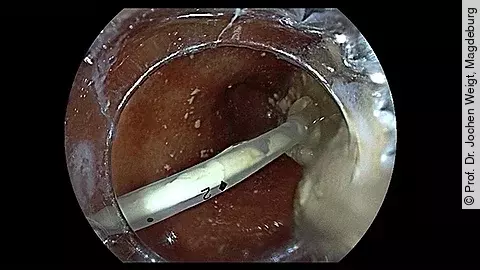

VideoEndoskopische Sichtkontrolle bei Ballondilatation

In unserem neuen Endoskopie-Video zeigt Ihnen PD Dr. Jochen Weigt, wie Sie während einer Ballondilatation – hier am Beispiel einer Pylorusdilatation – permanent die endoskopische Sichtkontrolle über den Dilatationsvorgang behalten können. Reinschauen lohnt sich!